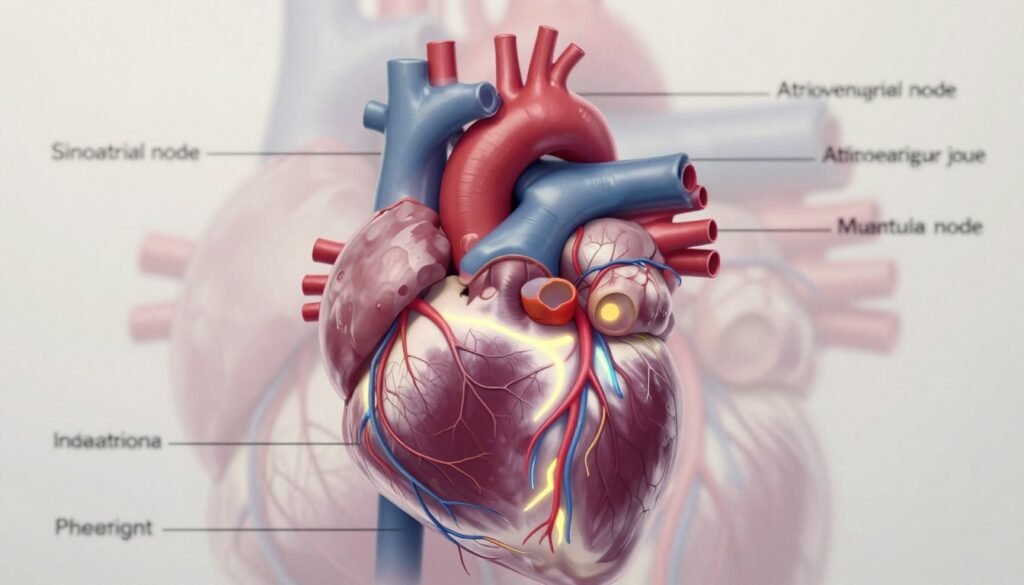

3. Ele Possui uma Rede Elétrica Autônoma que Dita o Ritmo

O coração tem seu próprio sistema de comando. Este sistema elétrico do coração é uma rede intrínseca e independente.

O nó sinusal, um pequeno grupo de células no átrio direito, é o maestro. Ele gera impulsos elétricos rítmicos que fazem as câmaras cardíacas se contrairem de forma coordenada.

Esses impulsos viajam por feixes especializados. Eles garantem que cada batida seja sincronizada e eficiente. A rede é autônoma, o que é incrível.

Isso significa que, mesmo sem o cérebro, o coração pode continuar batendo. Essa autonomia é essencial para nossa sobrevivência.